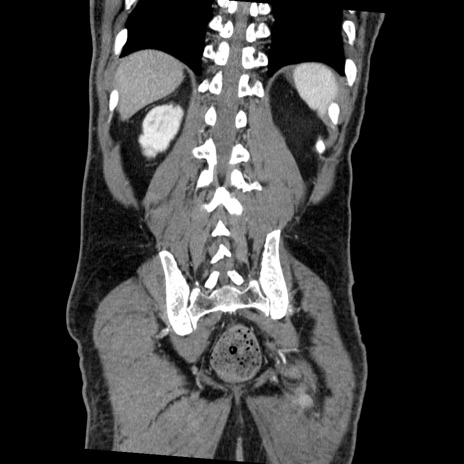

症例22(冠状断像)

【症例】50歳代男性

【主訴】腹痛

【現病歴】AVMからの被殻出血のため回復期リハ病棟入院中。 本日午後3時頃急に下腹部痛が出現した。

【既往歴】AVM、被殻出血、虫垂炎、高血圧

【身体所見】意識晴明、左半身不全麻痺、会話の理解は良好、36.5°C、腹部:膨隆、全体に板状硬、下腹部正中に圧痛点あり、反跳痛-、筋性防御不明、右下腹部にope scar

【データ】WBC 9400、CRP 0.06